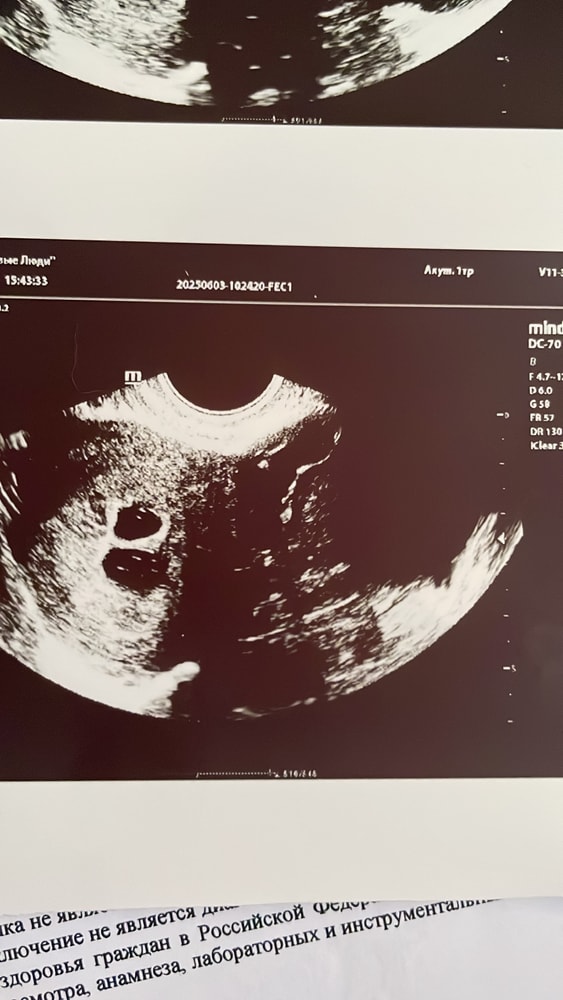

Ксения , тако аппарат( к сожалению,попала на сохранение сегодня 🥺 Делали снова узи,точно 2 Изображение Изображение

Ксеня, не волнуйтесь, все будет хорошо 🙏 двойное счастье 💞